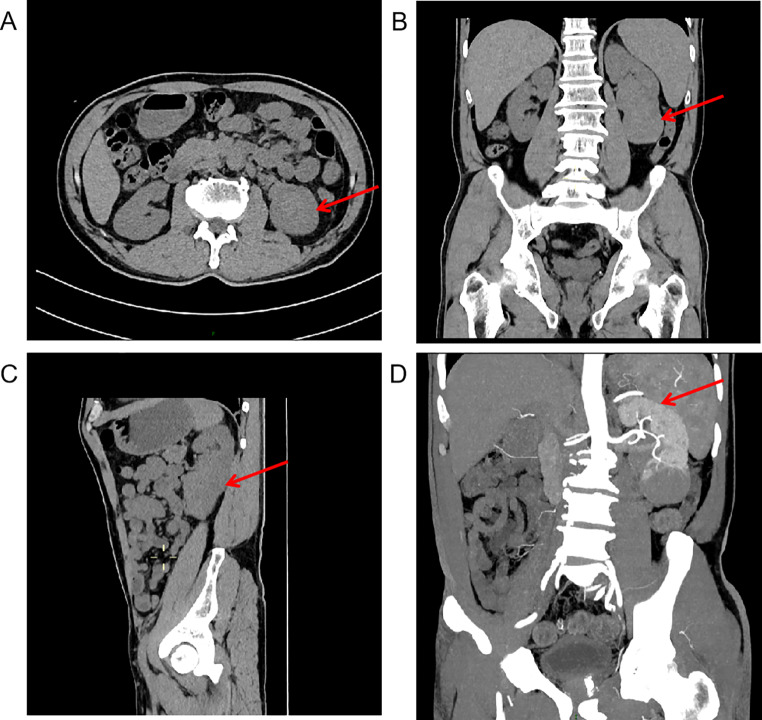

Case presentation: A 60-year-old male presenting with isolated thrombocytopenia was diagnosed with ITP during hematologic evaluation. Abdominal imaging incidentally revealed an 8.7 × 5.6 cm renal mass. Glucocorticoid therapy successfully stabilized platelet counts, enabling nephroureterectomy. Histopathological analysis demonstrated dense small lymphocyte infiltrates, with immunohistochemical confirmation of CD20 and Bcl-2 positivity establishing a diagnosis of MALT lymphoma. At six-month follow-up, the patient maintained disease-free status without adjuvant therapy.